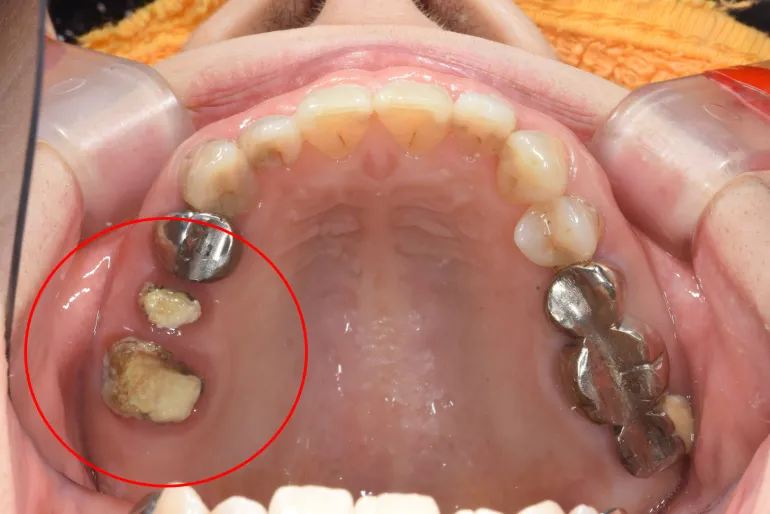

【症例4】

治療名

インプラント治療

治療説明

一番奥の歯が折れて抜歯が必要になったため、抜歯と同時に骨造成とインプラント埋入手術を行いました。その日に仮歯を装着し、3ヶ月後に最終的な型取りを行いました。痛みや腫れはほとんどなく、治療中も比較的自由に食事をしていただけました。

治療期間

4ヶ月

副作用・リスク

手術中に神経や血管を傷付ける可能性があります。痛み、腫れ、出血があります。インプラントの初期固定が取れない場合、治療期間が長引いたり、すぐに仮歯を装着できない場合があります。

料金

¥787,600(税込)